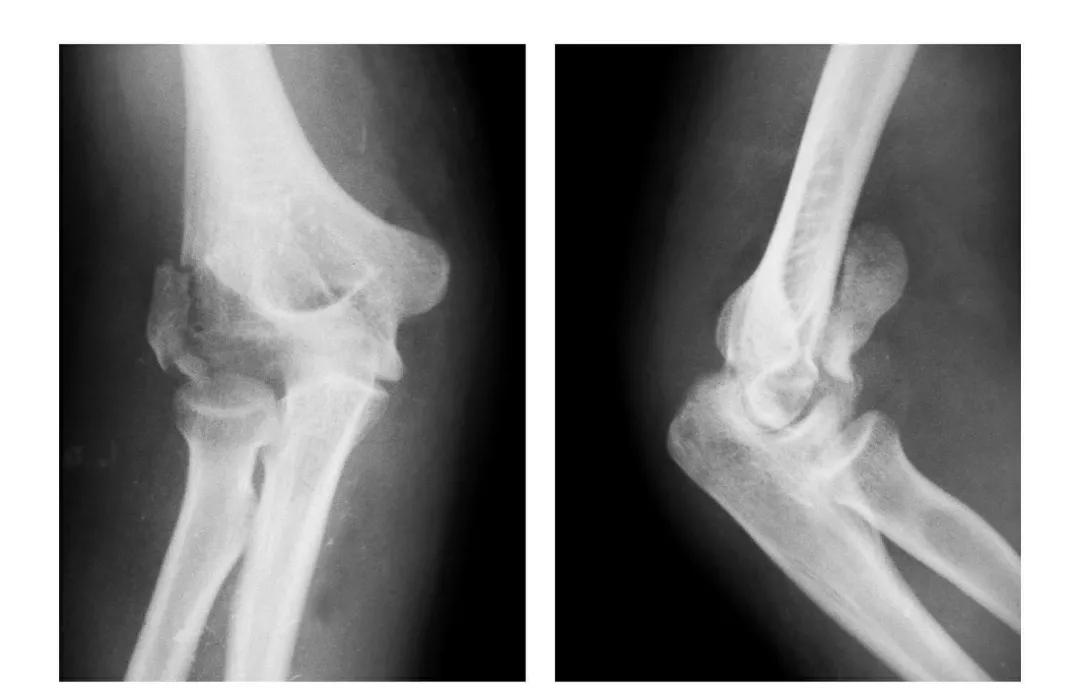

肱骨下端双髁骨折

例1:肱骨内髁及外髁骨折,该两髁骨块均呈向内、外翻转移位。

例2:肱骨内上髁Ⅲ度骨折并外上髁撕脱骨折。

例3:肱骨内上髁Ⅳ度骨折并外上髁撕脱骨折。